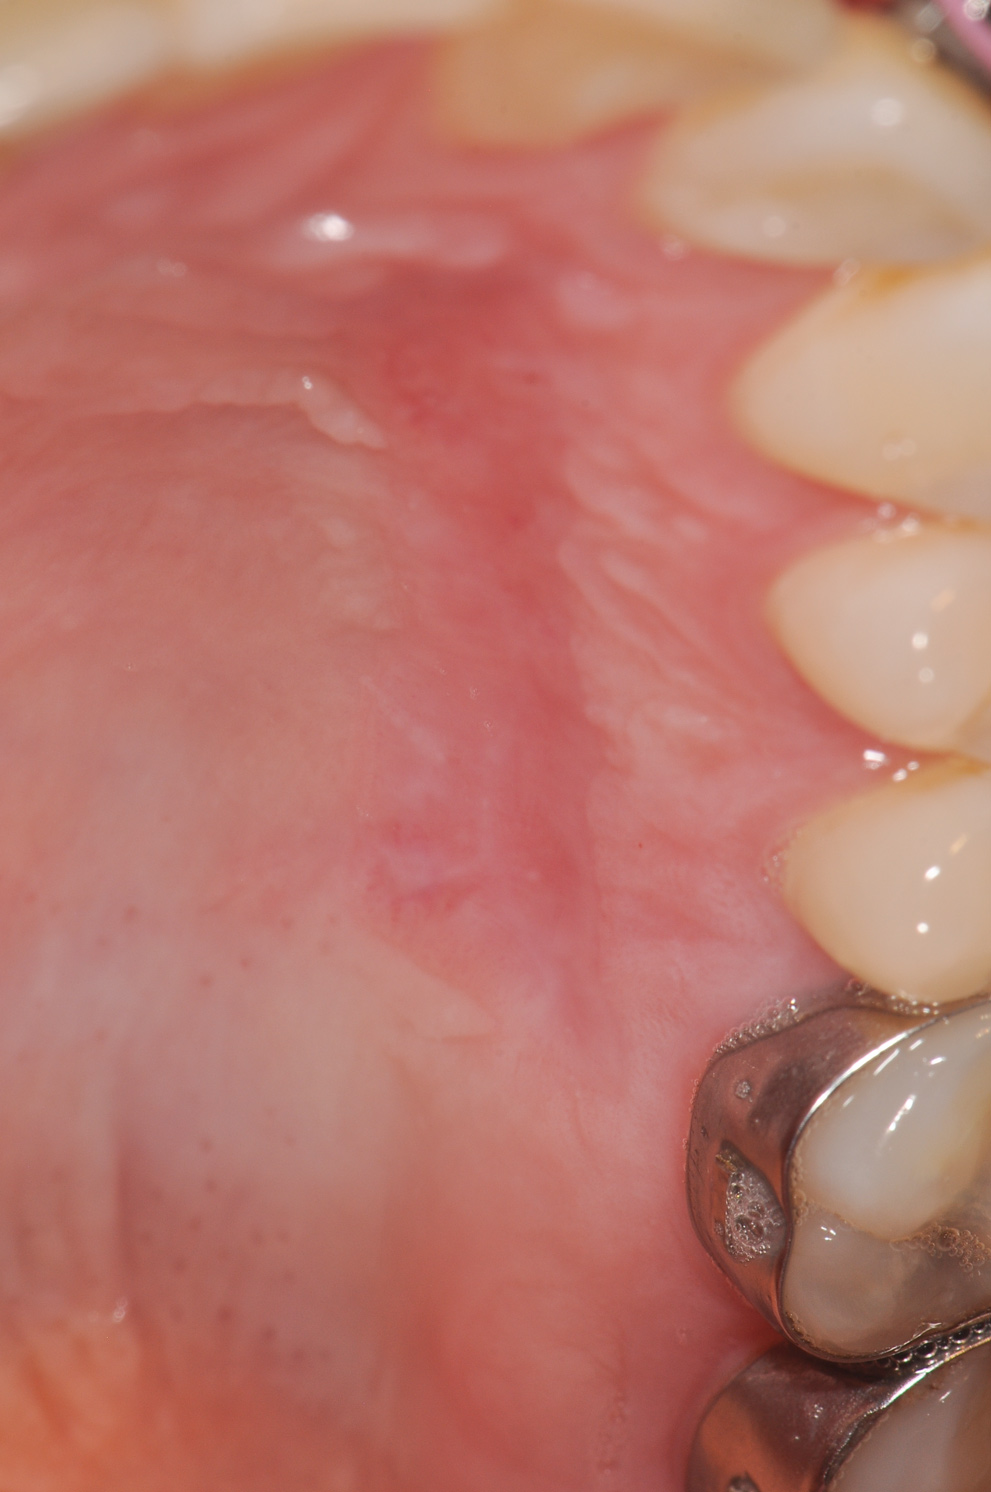

Although similar to the root coverage procedures mentioned above, gingival augmentation procedures not aimed at achieving root coverage are performed to facilitate plaque control, improve patient comfort, and prevent future periodontal recession. They may be used in conjunction with restorative, orthodontic, or prosthetic dentistry. The consensus report from the AAP's workshop group on soft-tissue non-root coverage procedures concluded that a specific minimum amount of keratinized tissue is not needed to prevent attachment loss when optimal plaque control is present; however, if plaque control is suboptimal, a minimum of 2 mm of keratinized tissue is needed. 12 A standard procedure that is recognized to predictably gain keratinized tissue is the use of an autogenous gingival graft.12 Figure 5 through Figure 8 demonstrate the healing progression of a patient with poor oral hygiene whose mucogingival defect was treated with a free gingival graft and L-PRF from the patient's own blood.

(5.) Pretreatment photo of patient with recession to be treated with a free gingival graft (harvested from the palate) and L-PRF.

Figure 5

(6.) Postoperative view of the graft donor site after 3 weeks.

Figure 6

(7.) Postoperative view of the graft recipient site after 3 weeks showing healing progress with poor oral hygiene.

Figure 7

(8.) Postoperative view of the graft recipient site after 6 months showing healing progress with poor oral hygiene.

Figure 8